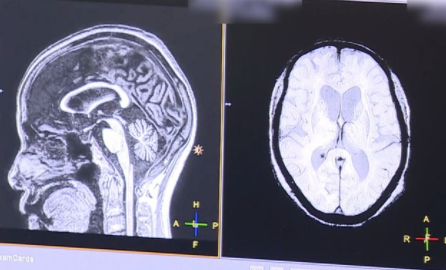

2018년 10월에 뇌 MRI 보험적용이 바뀌게 됩니다. 2018년 10월 이전에는 중증 뇌질환환자로 의사가 인정하는 경우에만 제한적으로 건강보험 적용이 되었습니다. 해당 상병으로는 뇌출혈, 외전증, 뇌경색 등이 있습니다.

하지만 2018년 10월에는 뇌혈관 및 뇌 MRI 가 건강보험 적용이 확대 되었습니다. 경증인 뇌질환이나 신경학적으로 이상이 있거나, 검사상 이상소견이 있다면 건강보험이 적용이 가능해졌습니다.

그리고 뇌질환이 의심되는 두통이 있거나, 어지러움이 있고 신경학적 검사를 실시한 경우에도 건강보험이 적용이 되어서 많은 국민들의 부담이 줄어들었습니다.